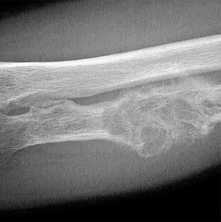

2. Рентгенография при эностозе (костном островке):

• Гомогенный участок уплотнения, угасающего к периферии с последующим переходом в нормальную трабекулярную структуру:

о Края участка имеют вид щетки; иногда могут быть звездчатыми

• Отсутствует кортикальная деструкция

(Слева) Рентгенография в ПЗ проекции: типичный крупный костный островок. Равномерный участок склероза с краями в виде щетки, которые переходят в нормальную кость. Четкий склерозированный край отсутствует.